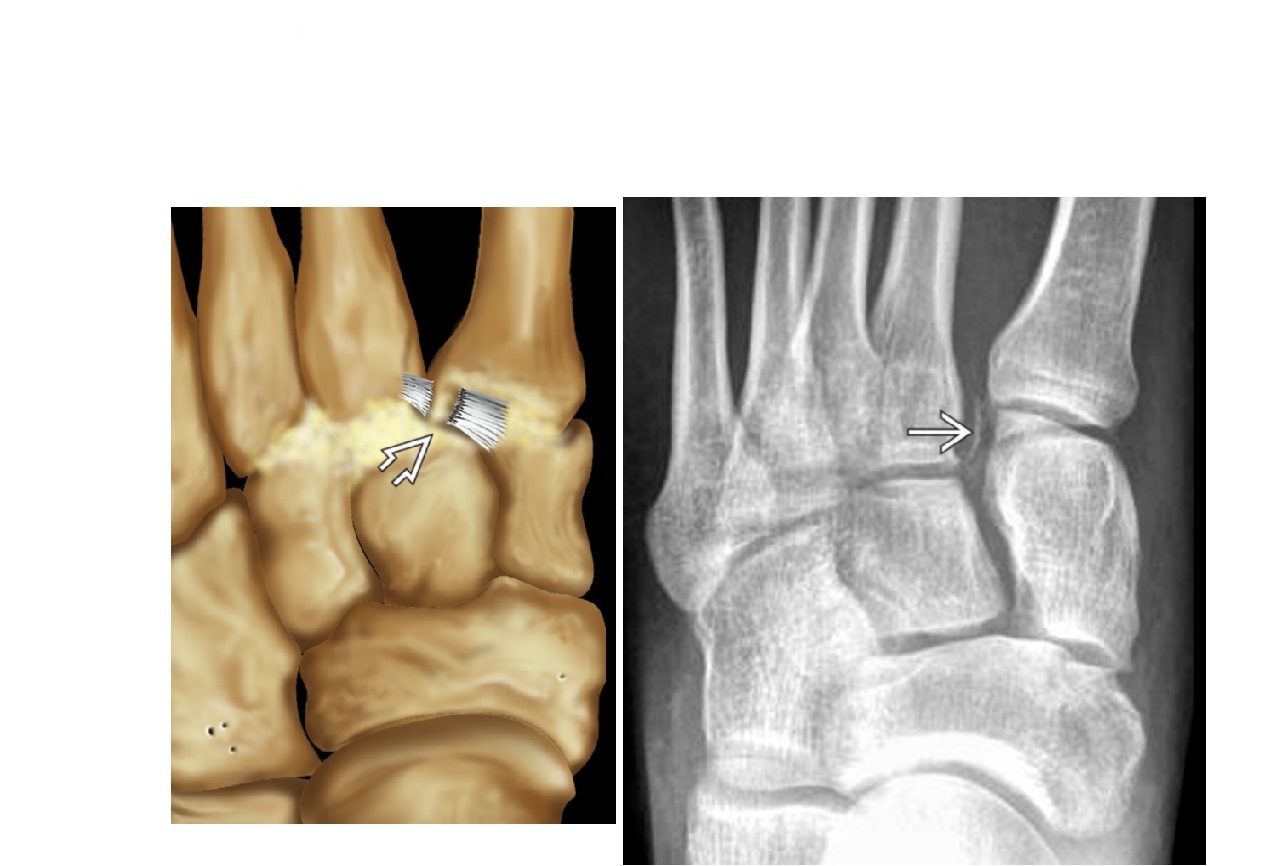

22

Patterns of Lis francs fracture/dislocations?

A

Homolateral = all tarsal move lateral

Divergent = 1st MT goes medial and 2-5th goes lateral

Fleck sign = in-between the 1st and 2nd MT = avulsion of the LF ligament

LF ligament connects the medial (1st) cuneiform to the 2nd metatarsal base on plantar aspect